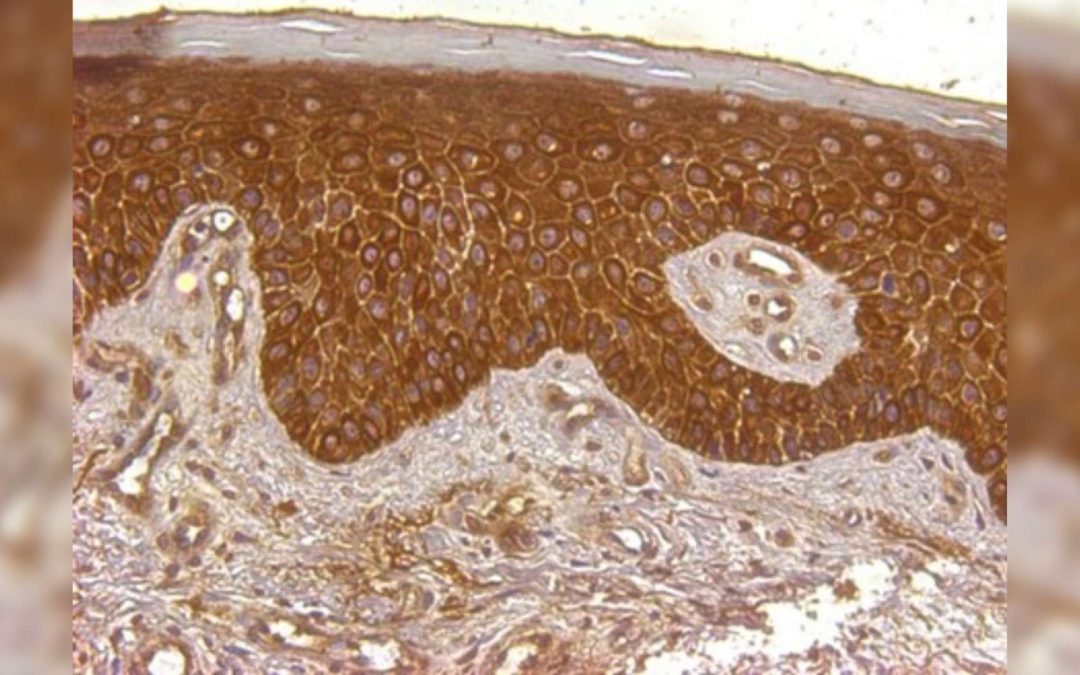

![[Syndrome de Cloves] Quand l’étude d’une maladie rare permet d’avancer sur des maladies plus répandues](https://wordpress-test.app.u-pariscite.fr/wp-content/uploads/2024/06/Lupus_Nephritis_2-Canaud-1-1080x675.jpg)

18 juin 2024 | Recherche Santé

L’équipe de recherche Médecine Translationnelle et Thérapies Ciblées, dirigée par le professeur Guillaume Canaud à l’Institut Necker-Enfants Malades (Université Paris Cité, AP-HP, Inserm), internationalement reconnue pour avoir identifié l’alpelisib comme traitement...